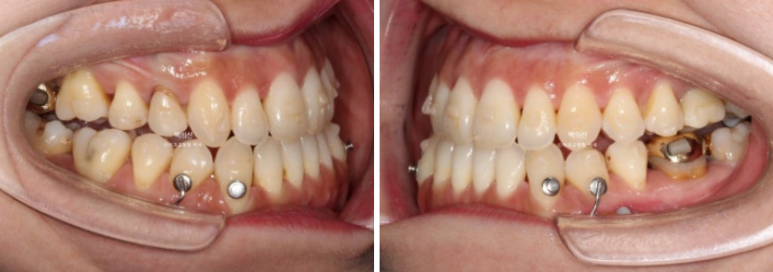

24.01~25.07

앞니 뿐만 아니라 어금니 반대교합도 함께 개선되었습니다.

중심선은 개선되었습니다.